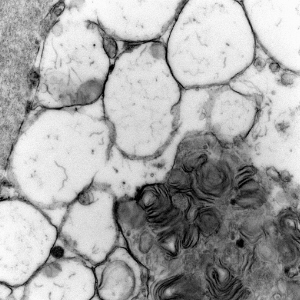

- ultrastructural findings useful in diagnosis

- lysosomal vacuoles with ill-defined contents

- may see glycogen granules

- "zebra bodies" in MPS

- lipopigments in the form of curvilinear profiles (like in NCL)

Lysosomal vacuoles and zebra bodies in mucopolysaccharidosis (mitral valve)